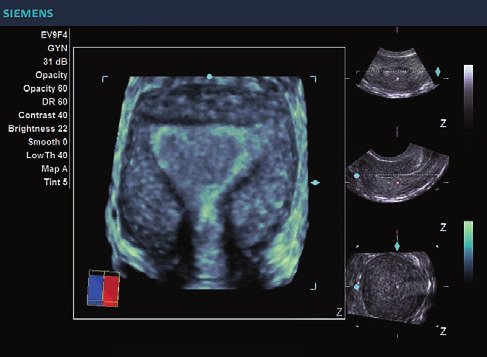

Das Siemens Acuson X300 PE ist ein mittelklassiges Herz-Kreislauf-Ultraschallgerät mit gemeinsamen Servicefunktionen. Die Premiumedition verfügt über 4D-Technologie und eine doppelte Auswahl an Sonden; zusammen mit vielen hochwertigen Funktionen ist sie in einem mittleren Preissegment erhältlich. Das Siemens ACUSON X300 PE bietet eine Vielzahl von Lösungen, einschließlich allgemeine Bildgebung, interdisziplinäre  Dienstleistungen, OB/GYN, Kardiologie, Urologie, Endokrinologie, Notfallmedizin und viele andere fachspezifische Anwendungen.

• Features: 3D, 4D, Farb/Doppler

• Gynäkologie/ Geburtshilfe

• Gynäkologie